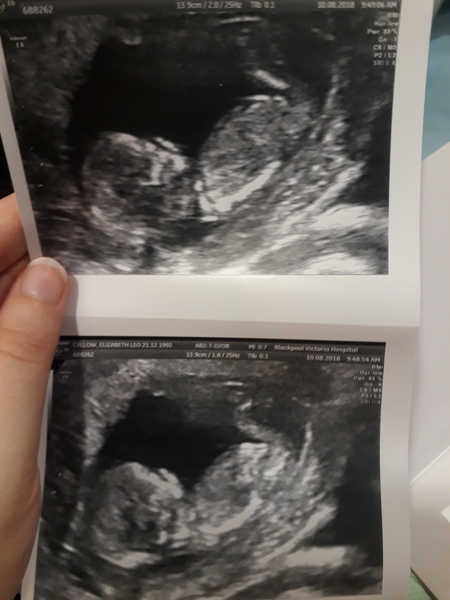

We got our scan Friday it was lovely. All went well and baby wiggly and started sucking it's hand aha. I think it's a boy, anybody else fancy a guess? Aha. Found out defo due on the 14th :)

Baby bean is all good

Everything looked great and how it should do the lady said just waiting for the blood test now for the downsyndrome but she measured the fold and said it was all normal :)

Measuring 12 +4 I thought I was 13 weeks today as last scan 2 weeks ago I was measuring 11 but they wasn't worried and said it's fine so now I'm the one worrying it hasn't grown that much? But the size has doubled is this ok ?

Due date is now 21st Feb

@Alicejj8x beautiful pic!